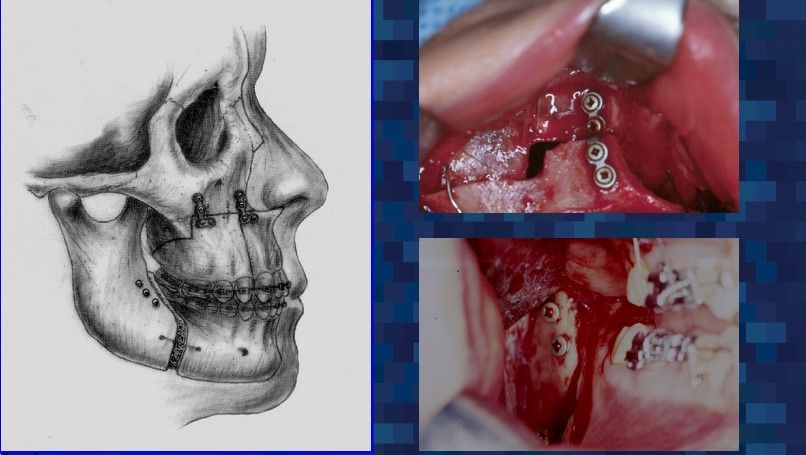

For over 30 years, Dr. Guerrero has made it his mission to improve the lives of his patients through specialized surgical care that restores function and comfort. Dr. Guerrero’s work embodies precision, compassion, and a dedication to patient well-being. Corrective jaw surgery is one of the advanced services offered, designed to address functional issues and enhance the quality of life for those who need realignment and reconstruction.